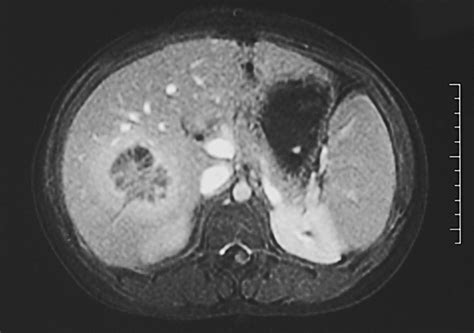

• Imaging Studies: Imaging techniques such as ultrasound, computed tomography (CT) scan, and magnetic resonance imaging (MRI) can visualize the abscess and determine its size and location.

• Percutaneous Drainage: A needle or catheter is inserted through the skin into the abscess to drain the pus. This procedure is often guided by ultrasound or CT scan.